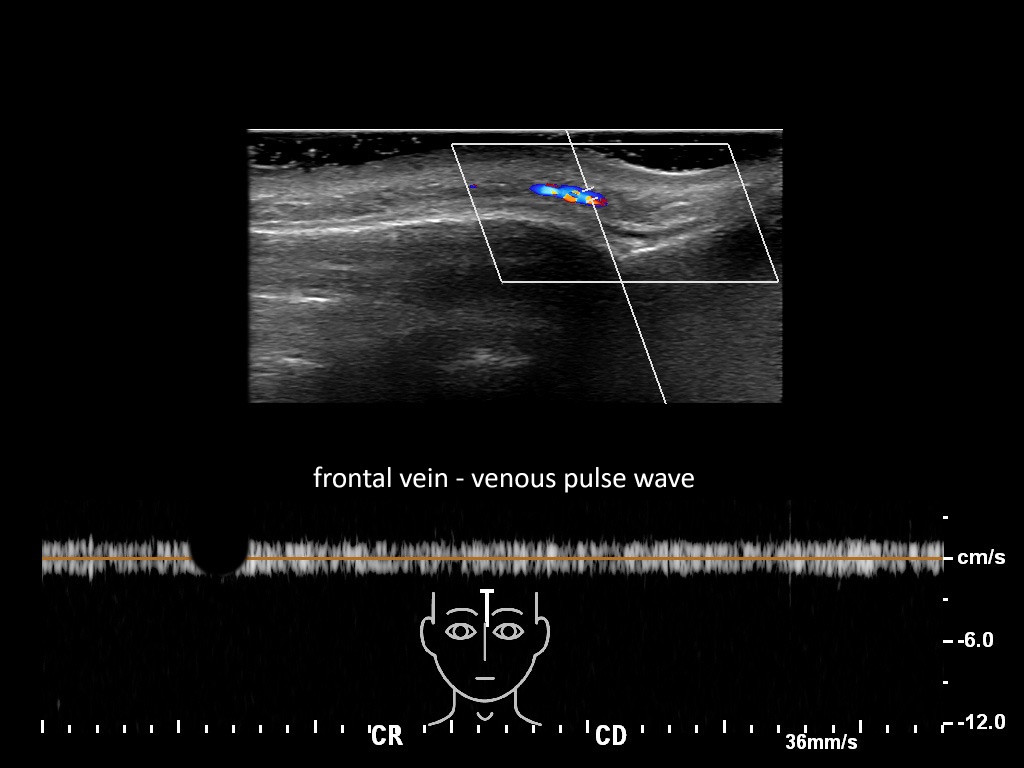

In this section you will learn more about the different layers of the face with the use of ultrasound. When you click on the secondary ultrasound image, you will see the different structures as an overlay. This will help to train yourself to recognize the different layers of the face.

Study the first image to recognize the different layers. If you are sure about the layers, swipe to the second image to view the answer (if applicable).